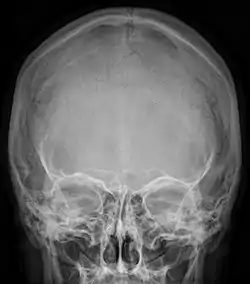

Radiograph of the skull showing an interparietal bone between the occiput and parietal bones

In humans, it corresponds to the upper portion of the squama of the occipital bone that lies superior to the highest nuchal line and is completely fused to the supraoccipital. However, in some individuals this portion remains separate from the rest of the occipital bone throughout life. In such cases, this separate bone is particularly referred as Inca bone. Inca bones in humans were first found in the skulls of contemporary indigenous peoples of the southern Andes as well as in those of mummies of the Inca civilization. Although the Inca bone was originally encountered as a variation in South American and Latin American cranial remains, the variation occurs in people from all geographic regions of the world and is by no means indicative of South/Latin American origin.